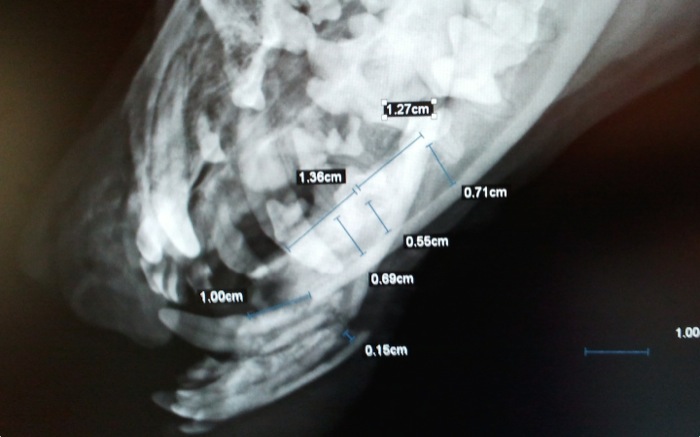

| Pruebas | La radiografía confirma lo que en la exploración se veía como un fragmento distal casi exento de tejido óseo donde fijar cualquier implante. |

Las medidas tomadas no ofrecen soluciones fáciles para un arreglo cómodo.

Del fragmento distal sobresalen los alveolos dentales limpiamente separados de las raíces de ambos caninos inferiores.